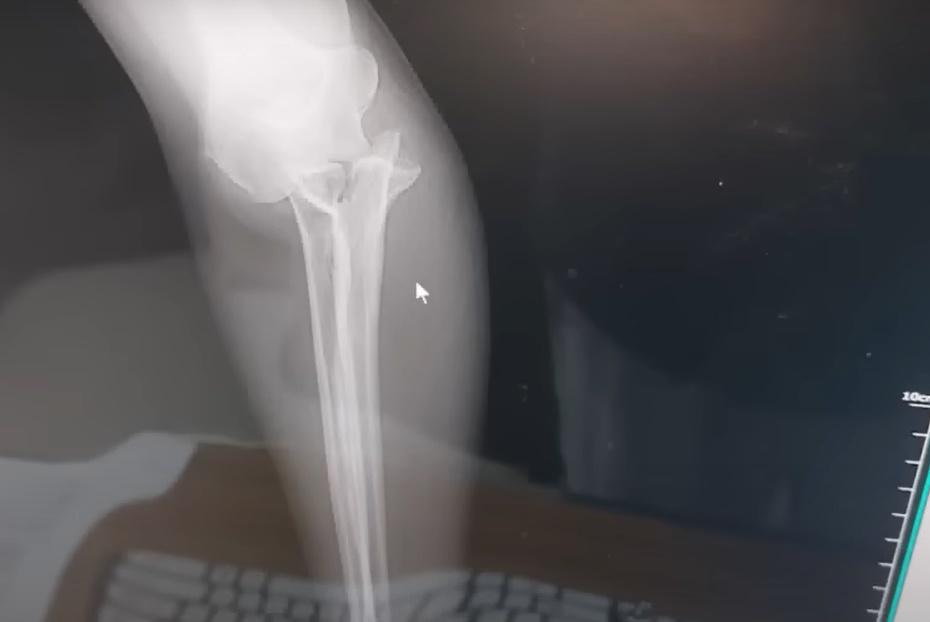

X光機發現她的手臂骨折,隨即要接受手術,以鋼板和骨釘螺絲固定骨頭。(YouTube) X光機發現她的手臂骨折,隨即要接受手術,以鋼板和骨釘螺絲固定骨頭。(YouTube) Beth與丈夫沒有將這個意外歸咎於大象,但勸誡其他遊客到峇里島接觸大象時要注意風險。(YouTube)

事後Beth被帶到酒店的前台敷冰,由於傷口不斷腫脹,便被送到醫院檢查,透過X光機發現她的手臂骨折,隨即要接受手術,以鋼板和骨釘螺絲固定骨頭。Beth又提到,園方原先承諾支付一半的醫療費用,不過後來不再回應夫婦的聯絡,直到外國傳媒報道事件,最近終於收到園方的賠償。Beth與丈夫沒有將這個意外歸咎於大象,但勸誡其他遊客到峇里島接觸大象時要注意風險。Beth提醒:「這將是一條漫長的康復之路。」